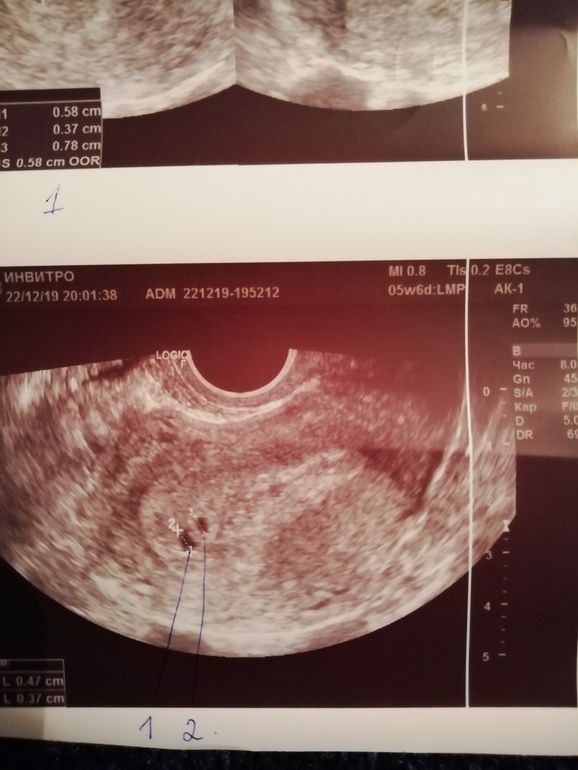

Двойня. Размер ПЯ не соответствует срокам. 😢

Вопросы про УЗИ, обследования и анализы: что, где, как, когда?Девочки дорогие, ситуация такая у меня. 7 циклов планирования и наконец то в 8ом цикле на 12 ДПО я увидела слабенькую вторую. Счастье, трепет. Даже не обратила внимания на светлокоричневую мазню в дни предполагаемых месячных. Сдала хгч на второй день задержки 141,4потом через 2 дня 473, 1. Успокоилась. Но как то потягивало живот и я пошла в ЖК. Там взяли мазок, записали на УЗИ 26.12. и назначила свечи утрожестан 200 на ночь. И я спокойно ждала УЗИ. И сегодня бац и розовая слизь вечером 😟 я собралась и на платное УЗИ побежала. Первое, что ошарашило, это 2 плодных яйца, НО размер их очень не соответствует сроку. По месячным 5 недель 6 дней, по УЗИ 4 недели 3 дня. 😢 Эмбриончиков не видно, а ведь уже сердечко должно стучать. Ещё признаки гематомы под вопросом. В общем врач ничего точно не сказала, предположила неразвивающуюся беременность, а так же позднюю имплатацию. Я не знаю что думать. Завтра пойду в ЖК без записи, надеюсь примут. УЗИ у меня теперь в ЖК 26.12. Прикладываю фото УЗИ. Пожалуйста поделитесь, у кого похожая ситуация была или есть🙏